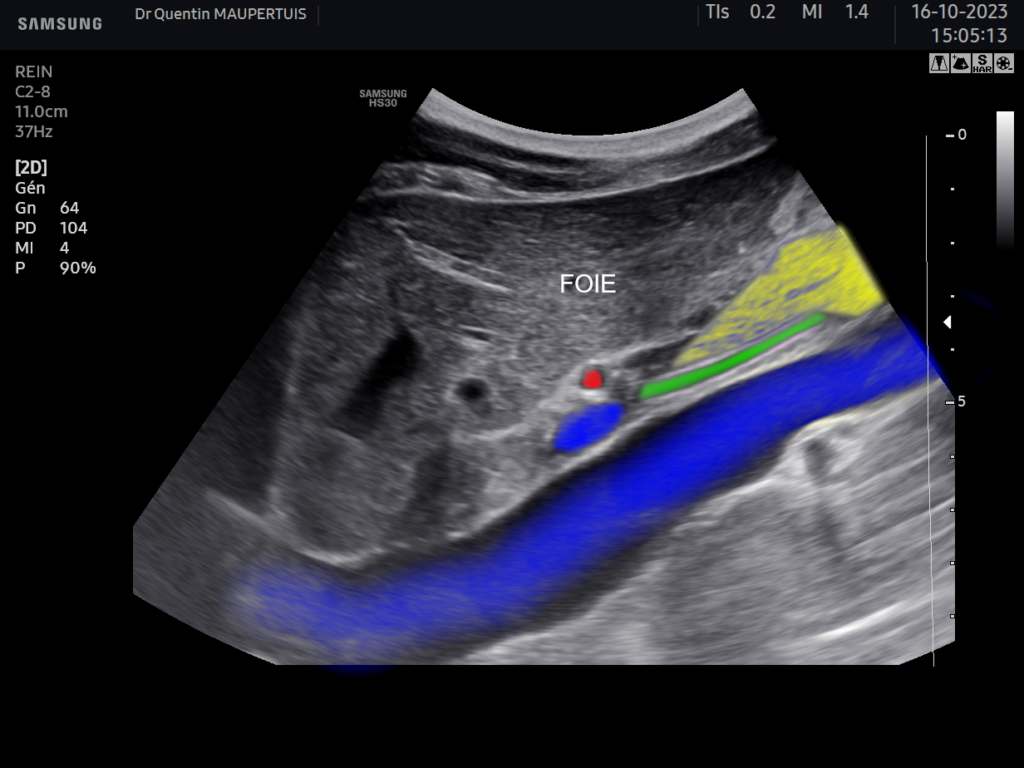

On retrouve sur l’image en dessous à droite :

En bleu la veine cave inférieure et le tronc porte,

En jaune la tête du pancréas

En rouge l’artère hépatique

En vert la voie biliaire principale.